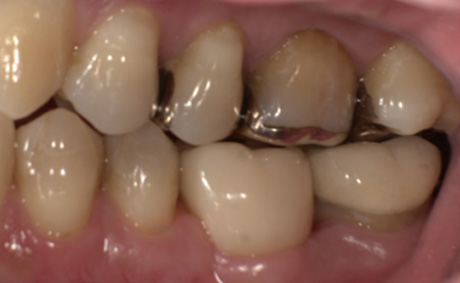

術前・術後の比較

| 術前 | 術後 |

|---|---|

![]() |